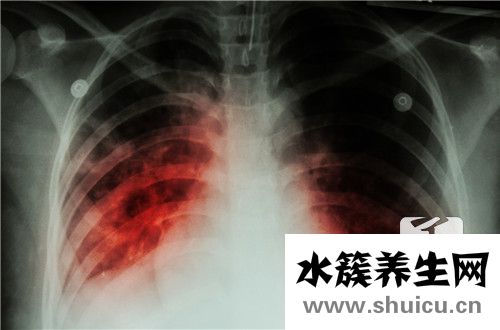

日常生活肺結核是常見病,會對患者的身心健康和日常生活產生很大影響。所以肺結核需要立即治療,肺結核治療需要一個漫長的全過程,所以在治療期間容易引起耐藥性。肺結核一旦引起耐藥,患者更擔心耐藥肺...